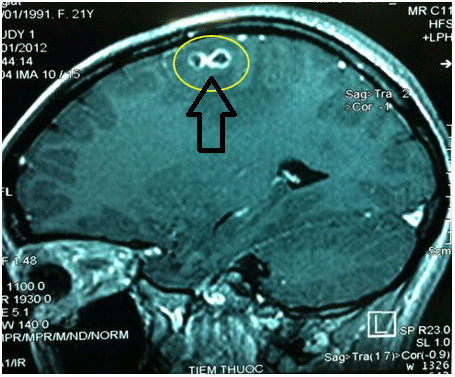

Dấu hiệu nhiễm sán chó Toxocara tổn thương hệ thần kinh trung ương (sán não): gây mệt mỏi, đau đầu, hay quên, tê tay nhức chân, giảm vận động, liệt, thậm chí dẫn tới,tử vong khi ấu trùng sán chó Toxocara di chuyển đến não.

Hình ảnh ấu trùng sán chó Toxocara trong não